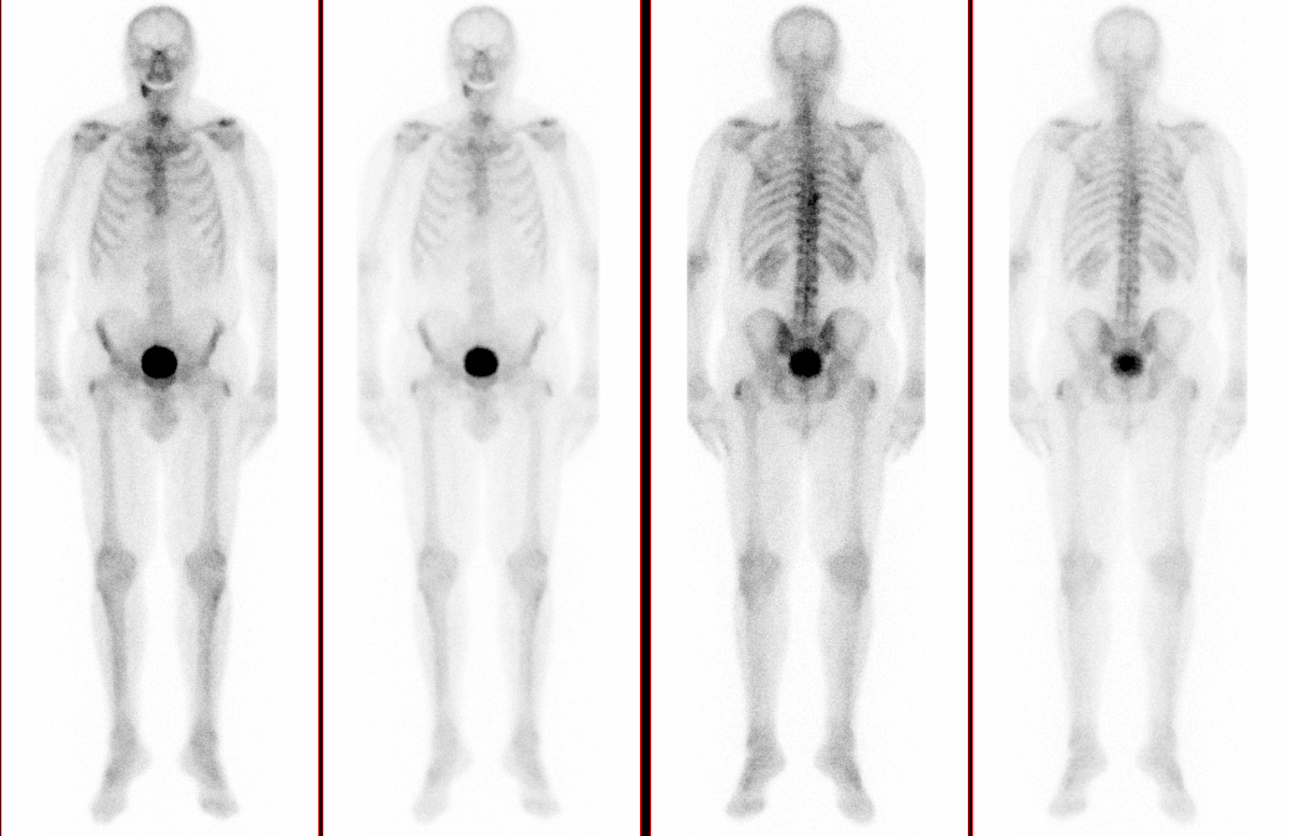

Bone Scintigraphy

Bone Scintigraphy – Whole-Body Imaging for Bone Metastases, Fractures, and Prosthesis Loosening Bone scintigraphy (also called skeletal scintigraphy) is a nuclear medicine imaging technique that visualizes the metabolic activity of the entire skeleton.